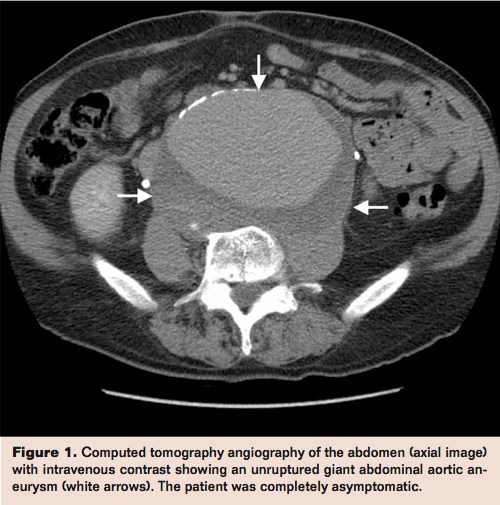

Computed tomographic angiography of the abdomen after administration of intravenous contrast showed a giant juxtarenal abdominal aortic aneurysm (AAA) measuring 14 cm in diameter (Figures 1 and 2, arrows) without any evidence of rupture. He was sent to the hospital for urgent vascular surgical treatment. On admission, his exam was unchanged and the laboratory data showed mild chronic anemia and normal creatinine.